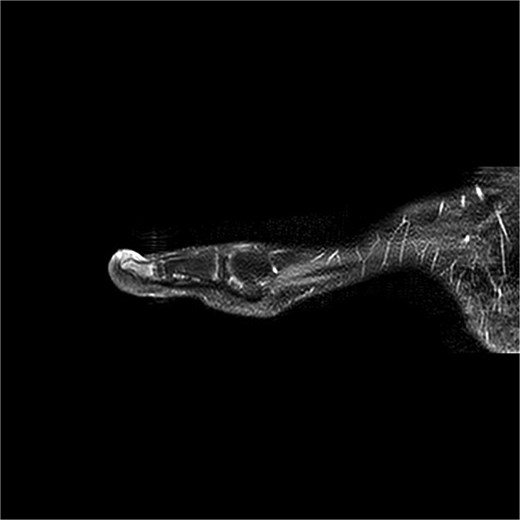

A 12-year-old male presented with pain and deformity of the right great toe (Fig. 1). MRI confirmed SE with osteomyelitis (Fig. 3). Bone cultures grew S. aureus and Staphylococcus lugdunensis with moderate growth in one of five samples. After 1 week of intravenous therapy, treatment was completed with oral dicloxacillin. At 17- and 39-day follow-up visits, the patient was pain-free with no signs of infection (Fig. 2).

Preoperative MRI from case 1 demonstrating SE and associated bone marrow edema.